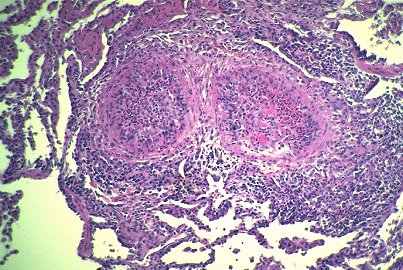

| Thrombosed pseudoaneurysm in the pancreas of a patient with polyarteritis nodosa. |

![]() |

Microscopic changes in the pancreas: polyarteritis nodosa

Here we can see an artery within the pancreas. At this point the walls have been eroded through and there is this large pseudo-aneurysm filled with thrombotic material. This process was initially called periarteritis nodosa by Kussmaul and Maier, but soon after the term polyarteritis nodosa became more popular, and nowadays it is really the preferred term because many different vessels are involved and it is really a transmural process, not a perivascular process.